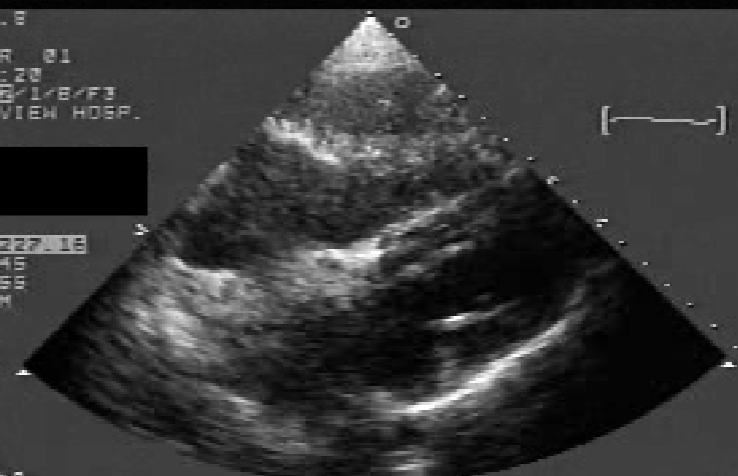

Myxoma

neoplasm that arises from endocardial tissue

80% located in LA

RA 2nd most common

usually attached by a stalk to the IAS

“pedunculated”

often arises from IAS

near region of fossa ovalis

Classic LA Myxoma

echogenic mass located in the body of the LA in systole and prolapses through the mitral orifice in diastole

causes stenosis if large enough

Myxoma 2D findings:

visualization of myxoma

allows detection, location, + sizing

exaggerated motion of myxoma

d/t prolapsing from LA into the LV